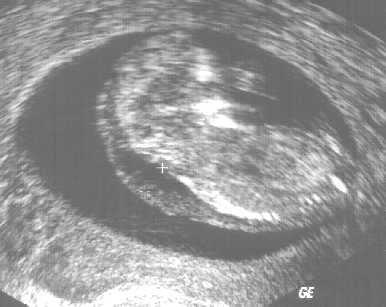

Am Ende des ersten Schwangerschaftsdrittels findet man häufig eine Wasseransammlung (Nackentransparenz) unter der Haut des kindlichen Nackens. Ist diese Schicht größer als normal, kann dies auf chromosomale Anomalien oder andere Erkrankungen des Kindes hinweisen (z. B. Herzfehler).

Durch die Messung der kindlichen Nackentransparenz (NT-Messung) kann von der 12. bis 14. Schwangerschaftswoche durch zertifizierte Ärzte eine individuelle Risikoberechnung in Bezug auf die Trisomie 21 durchgeführt werden.

Die Messung erfolgt durch eine vaginale oder abdominale Ultraschall-Untersuchung.

| unauffällige Nackentransparenz | exakte Darstellung im hochauflösenden Ultraschall | auffällige NT, weitere Diagnostik erforderlich! |

Diese Untersuchungen bieten keine Diagnose, sondern eine individuelle Risikoabschätzung. Ein auffälliges Testergebnis bedeutet nicht, dass das Kind eine Chromosomenanomalie oder einen Herzfehler hat, sondern es zeigt an, ob ein höheres Risiko besteht. Dann sollte ggfs. eine weiterführende Diagnostik erfolgen. Umgekehrt kann das Risiko bei entsprechender NT-Messung sich auch vermindern. Ein sicherer Ausschluss von Chromosomenstörungen ist letztlich nur durch eine Fruchtwasserpunktion oder Chorionzottenbiopsie möglich.